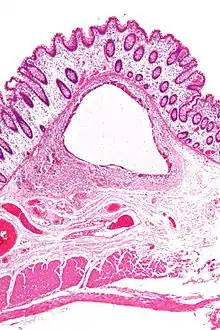

Micrograph showing large bowel wall with pneumatosis cystoides intestinalis, a generally benign subset of pneumatosis intestinalis. H&E stain.